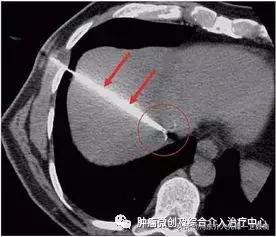

肝癌的治疗中还有一种方法,叫做消融,就是用一根会发热的电极,放到肝癌里面将肿瘤“烧”死。

射频消融(RFA):RFA的治疗原理是利用高频电流(375~500kHz)通过针状电极与接地板在体内形成回路,交替电流的激发引起电极周围组织离子高频振动,相互碰撞摩擦产生热能,局部组织温度升高,蛋白质变性,从而导致组织不可逆凝固性坏死,达到杀死肿瘤细胞的目的。病变凝固坏死的“理想”温度约为60-65℃,但电极尖部周围的组织可吸收热量,因此必须加热到高于理想温度才能达到治疗目的。然而,温度>100℃可引起组织脱水和炭化,导致阻抗增加,从而阻止能量的进一步沉积,因此最佳治疗温度约为85-90℃。

8.CT/B超引导下肿瘤射频消融及碘125粒子植入介入治疗。